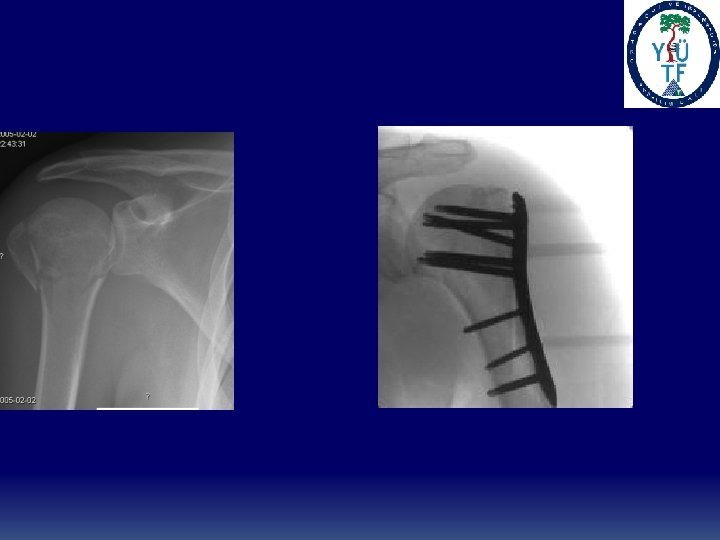

Proximal Humerus Fractures ü Treatment ü Minimally displaced fractures- Sling immobilization, early motion ü Two-part fracturesüAnatomic neck fractures likely require ORIF. High incidence of osteonecrosis üSurgical neck fractures that are minimally displaced can be treated conservatively. Displacement usually requires ORIF ü Three-part fractures üDue to disruption of opposing muscle forces, these are unstable so closed treatment is difficult. Displacement requires ORIF. ü Four-part fractures üIn general for displacement or unstable injuries ORIF in the young and hemiarthroplasty in the elderly and those with severe comminution. High rate of AVN (13 -34%)